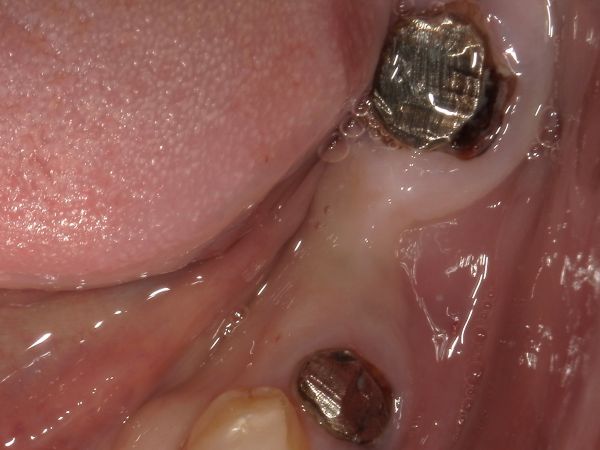

まずは、ブリッジの土台の歯を残せるかどうかを判断しました。左下7番目の歯を拡大した写真がこちらになります。

左下7番目の歯には大きな金属の土台があり、よく見ると土台の周囲には茶色い虫歯が広がっているのが分かります。つまり、土台を外して虫歯をとっていくと歯茎の外側にほぼ歯がない状態となってしまいます。